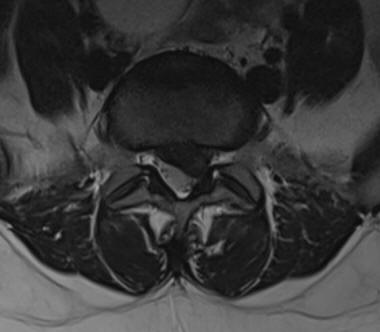

29-DECEMBER-2019  MASHAEL ISMAEEL MUHAMED  46 YEARS  HUGE EXTRUDED DISC L5-S1 WITH LEFT FORAMINAL OCCLUSION.

The patient came to the clinic 28-December-2019 with severe LBP and agonizing left sciatica, pain and numbness left S1 territory for 2 months. MRI lumbar spine performed 23-December-2019 showing huge extruded disc L5-S1 with left foraminal occlusion.

Fig-1: The extruded disc L5-S1.